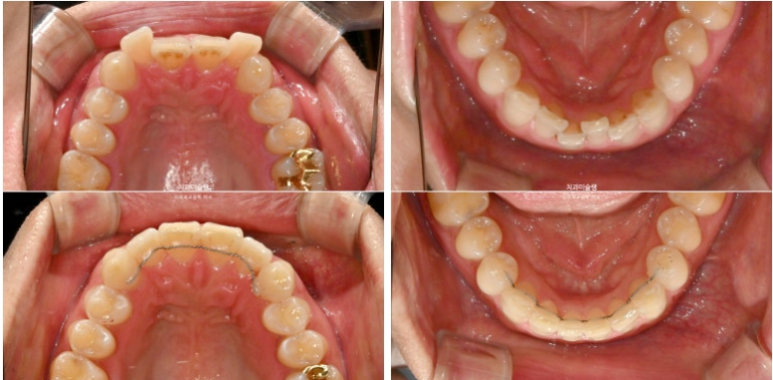

MTA 장치와 설측 2D 장치중 보이는 것 상관없다 하여 MTA 추천드렸습니다.

윗니배열은 완벽하며

아랫니 배열이 조금 부족합니다.

약 2개월간 교정을 더 진행하여 10월, 드디어 장치를 뗍니다.

앞니만 교정하는 부분교정이기에 어금니 교합은 그대로 유지됩니다.

25.04~25.10

환자분이 투자한 기간과 비용 대비 아주 만족스러운 결과입니다.